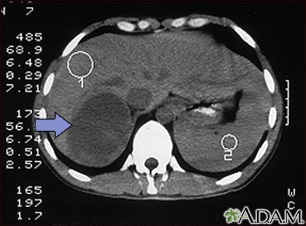

- Abdominal CT scan

- MRI of abdomen